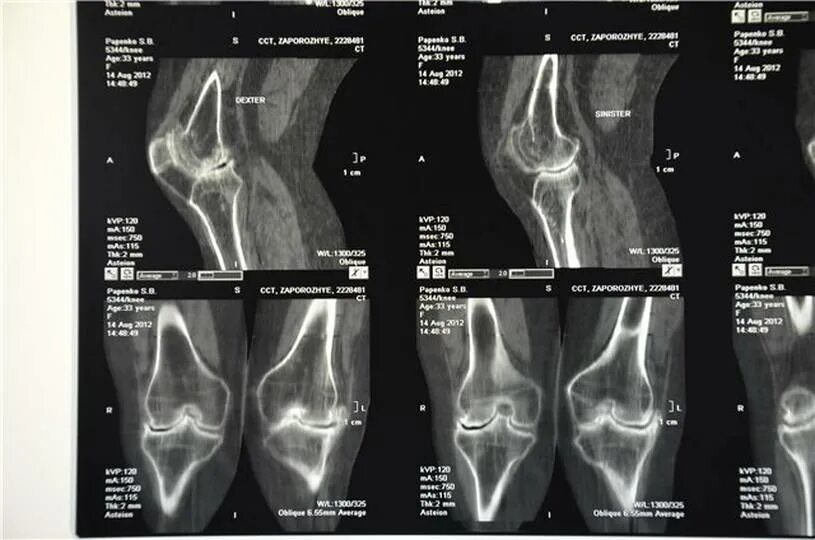

Гонартроз мрт